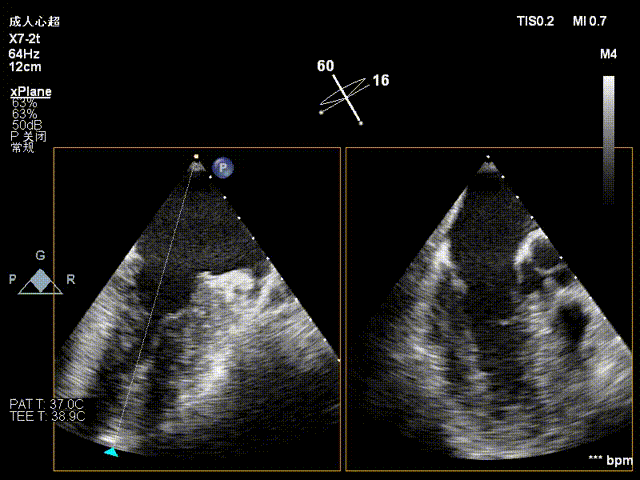

术前影像

二尖瓣后瓣腱索断裂并脱垂及关闭不全(重度)